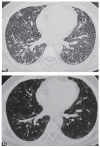

Fig. 1.

HRCT chest showing fibrotic, bronchiectatic and consolidative changes at presentation (a), and improvement after one year of therapy (b)